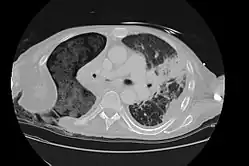

The Eloesser flap is a surgical procedure developed by Dr. Leo Eloesser in 1935 at the San Francisco General Hospital.[1] It was originally intended to aid with drainage of tuberculous empyemas, since at the time there were no effective medications to treat tuberculosis. The procedure was used extensively[2] until the development of effective antimicrobial therapy for tuberculosis in the late 1940s and early 1950s.[3] It is still used occasionally for chronic empyemas.[4][5]

As originally described by Dr. Eloesser, the procedure started with cutting a 2 inch wide, U-shaped flap of skin on the side of the chest wall underneath the axilla and scapula. The section of rib under the top of the flap was also removed. The finger-like skin flap was then inserted into the cavity made in the chest wall and sewn into the inner pleural lining of the chest. The edges of the incision are then brought together.[1] The flap allows for 1) passive drainage of the pleural space and 2) negative pressure to develop in the thoracic cavity due to it being easier for air to escape than to enter the chest. The lung can then expand to the chest wall and seal the inner opening of the flap.[3] Other surgeons have subsequently proposed modifications to the procedure.[6]

The Eloesser flap is still utilized for patients with chronic empyemas who have not improved despite being treated with antibiotics and first line surgical procedures to remove pus and re-expand the lung such as decortication or video-assisted thoracoscopic surgery.[4] Often they are thought to be too ill for more definitive procedures such as a major thoracotomy or muscle flap transposition.[5] In a recent case series, the most common reasons to need an Eloesser flap were parapneumonic effusions and postresection empyemas, with only 9% done for tuberculosis.[4]